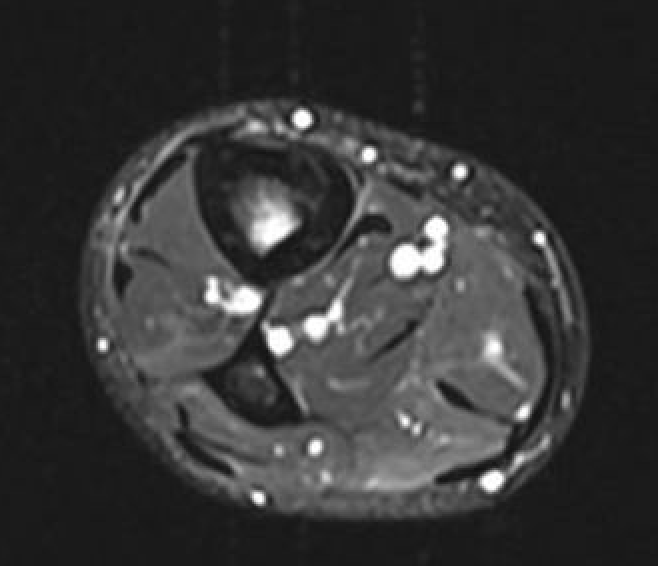

MRI

Fredericson Classification of Medial Tibial Stress Fractures on MRI

Grade 1: Periosteal edema

Grade 2: Bone marrow edema on T2

Grade 3: Bone marrow edema on T1 and T2

Grade 4a: Intra-cortical stress changes

Grade 4b: Frank tibial stress fracture